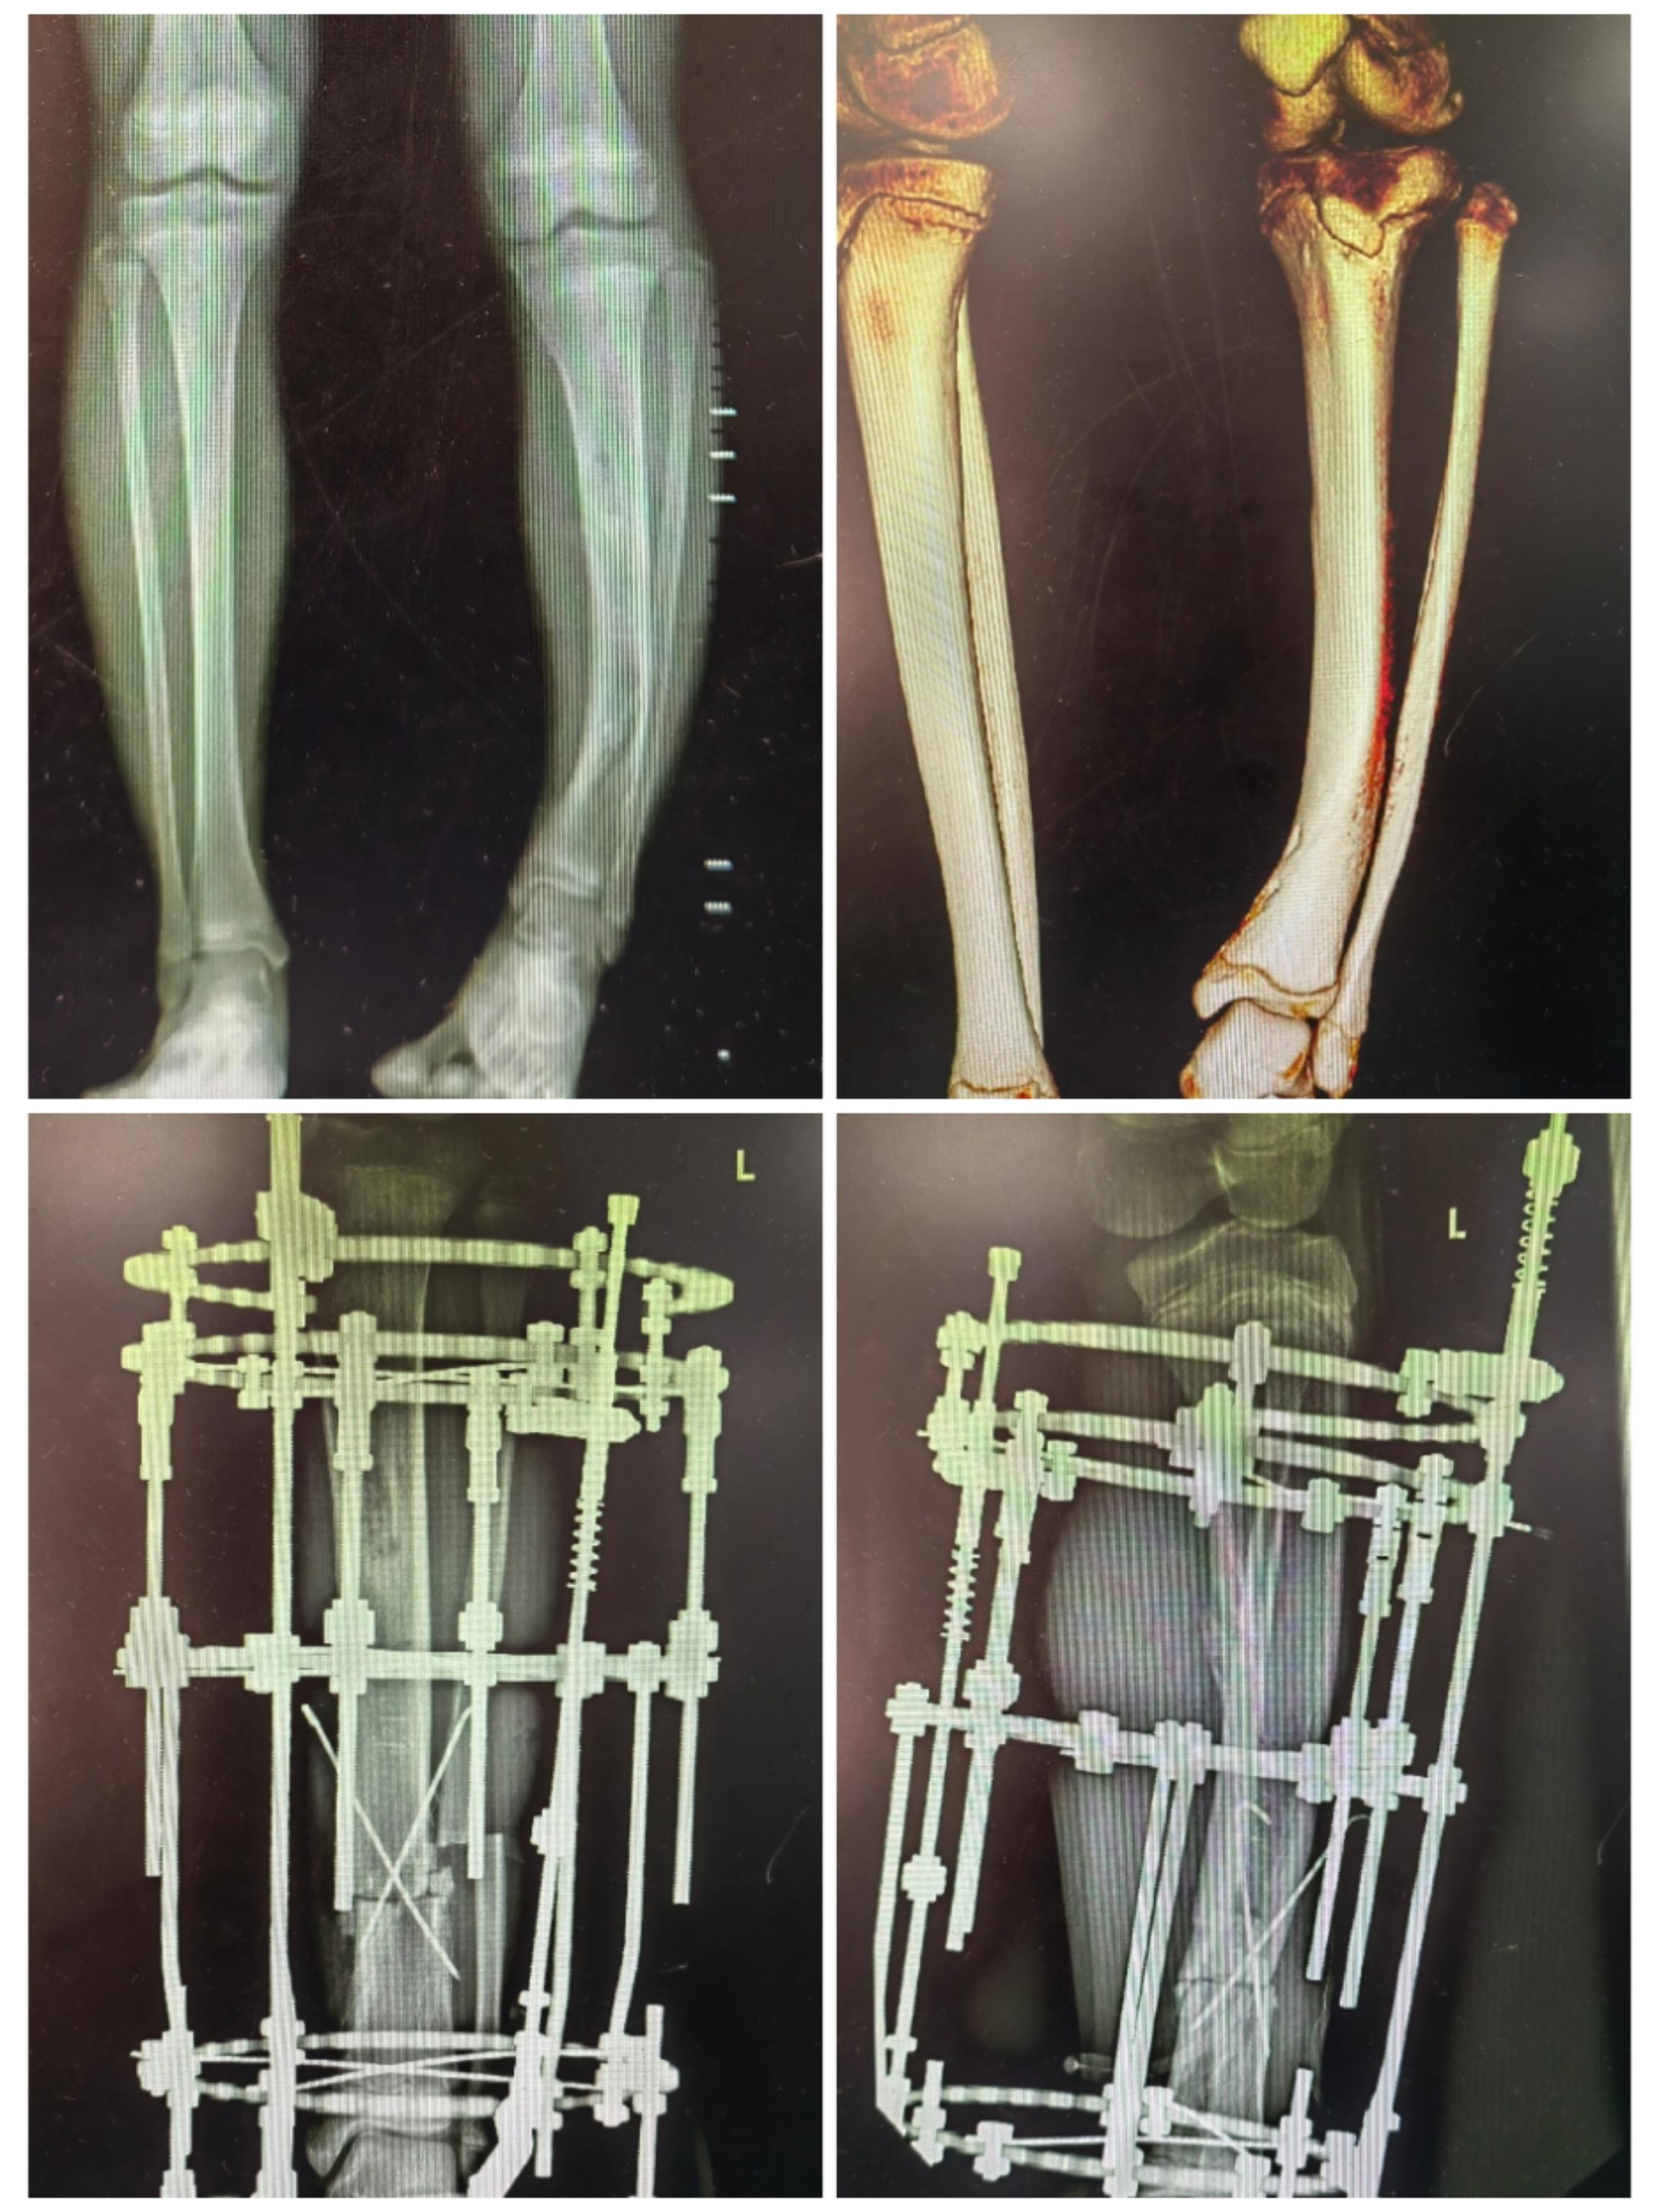

部分病例展示

儿童胫骨发育畸形—截骨矫形环型外支架固定